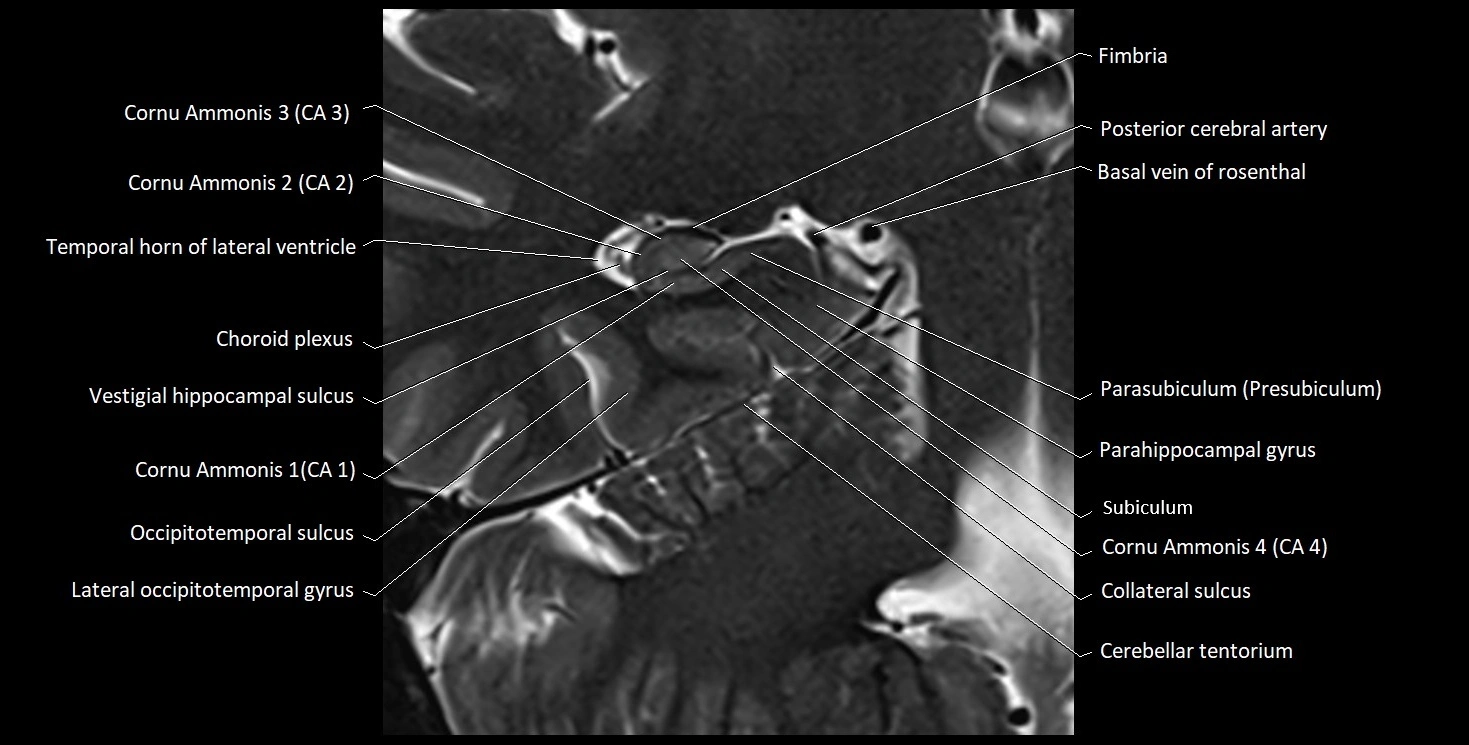

MRI Appearance

T1-weighted images:

• Alveus: Thin linear high signal band (due to myelinated fibers) overlying the hippocampal gray matter.

• Hippocampal gray matter: Intermediate signal intensity.

• CSF of lateral ventricle: Dark (low signal).

• Pathology:

• Sclerosis: Alveus becomes indistinct, with reduced T1 signal and hippocampal atrophy.

• Edema or gliosis: Diffuse hypointensity and blurring of alvear margins.

T2-weighted images:

• Alveus: Low signal line overlying brighter hippocampal gray matter.

• CSF: Bright hyperintense.

• Gliosis or demyelination: Causes increased signal in the alvear region.

• Hippocampal sclerosis: Gray-white differentiation becomes indistinct.

• Edema: Hyperintense change surrounding alveus.

MRI images

image